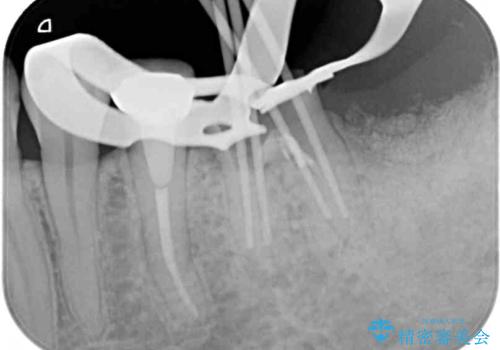

根管治療を行ったは、以前の治療で開けられて思われる穴が歯の内部に開けられており、炎症を起こしていました。

根管治療と合わせて、穴の開けられている部分を修復したところ、炎症による歯槽骨吸収に改善が見られました。